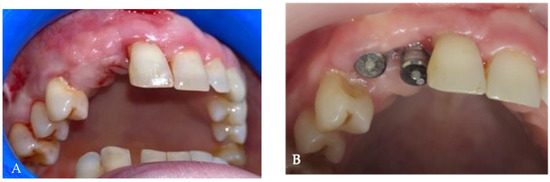

Background and Objectives: Alveolar ridge augmentation in the complex bone defect is a popular topic in implantology. Guided bone regeneration (GBR) is one of the most commonly applied methods to reconstruct alveolar bone. The application of a membrane is the fundamental principle of GBR. There are many membrane types used in oral surgery, but the advantage of the titanium mesh is the rigidity which provides space maintenance and prevents contour collapse. The smooth surface also reduces bacterial contamination. Using computer-aided design (CAD) and computer-aided manufacturing (CAM) in dentistry allows us to obtain the perfect architecture form of the mesh, which covers and protects the bone reconstruction. Case presentation: We present a surgical case of a 27-year-old female patient with severe aesthetic bone atrophy after a deficient odontectomy. Based on the GBR clinical applications, the technique consists of bone reconstruction and a customized titanium mesh application. Using mesh titanium in this case presentation was a reliable alternative to perform a lateral alveolar bone augmentation and reconstruct ridge deformities before reaching an ideal implant placement. Conclusions: According to our case report, the customized titanium mesh could be a valuable option for guided bone regeneration in aesthetic maxillary defects. Full article